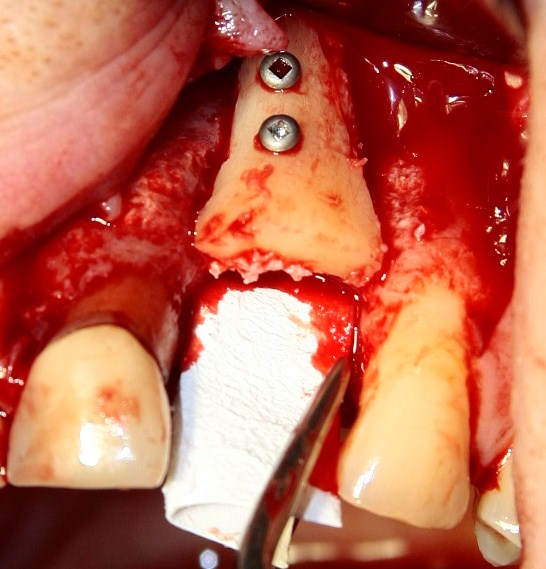

После чего мы адаптируем и фиксируем костный блок в области дефекта:

Если вы обратили внимание, костный блок и его ложе неконгруентны, между ними есть пустое пространство. Если оставить всё так, то в промежуток между костью челюсти и блоком врастет слизистая оболочка (она регенерирует намного быстрее кости), и вместо нормальной кости мы получим секвестр на винтиках. Чтобы этого не произошло, используется барьерная мембрана, в данном случае коллагенновая BioGide компании Geistlich:

В процессе забора костного блока мы собрали небольшое количество аутокостной стружки — помещаем ее между пересаженным блоком и костью челюсти. В принципе, этот этап необязателен — даже в изолированном мембраной кровяном сгустке нормально запускаются процессы остеогенеза — и у меня по этому поводу есть ряд наблюдений. Поскольку «пришить» мембрану пинами к твердому костному блоку проблематично, для ее фиксации я использую очень короткий (4 мм) винт: